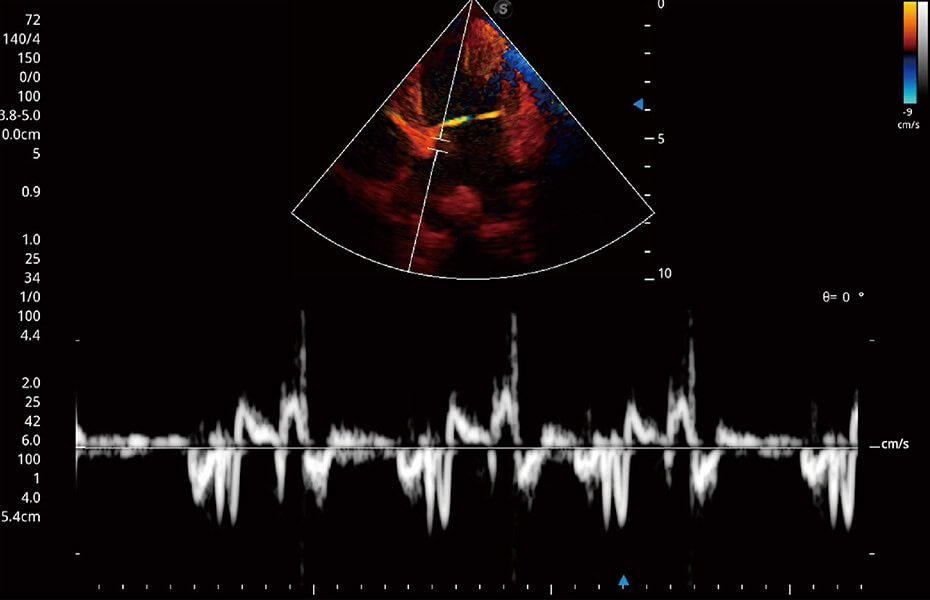

ProPet 60 作為一款高端臺式動物超聲設(shè)備,為動物醫(yī)生的日常診斷提供了一系列貼合動物臨床需求、解決臨床實際問題的高級成像功能。憑借全系列高清探頭,滿足醫(yī)生對腹部、心臟、生殖、淺表、肌骨等成像的所有需求,切實幫助您提升檢查效率,提高診斷信心。

獸用彩色多普勒超聲診斷系統(tǒng)